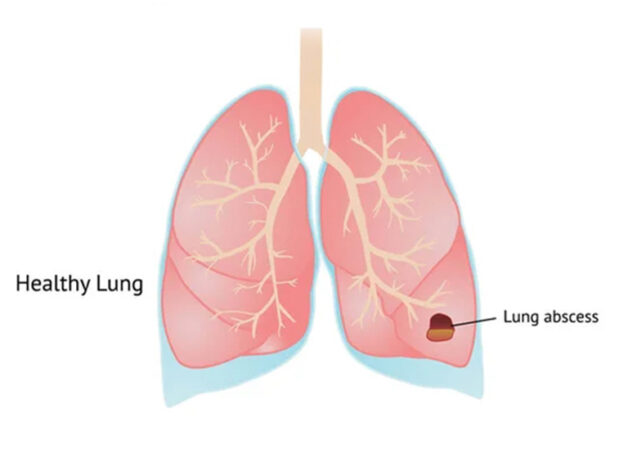

Áp xe phổi Hướng dẫn phòng tránh và xử lý kịp thời

áp xe phổi

- Áp xe phổi Giải mã những thông tin quan trọng cần biết

- Áp xe phổi Giải mã nguyên nhân, triệu chứng và hướng xử trí